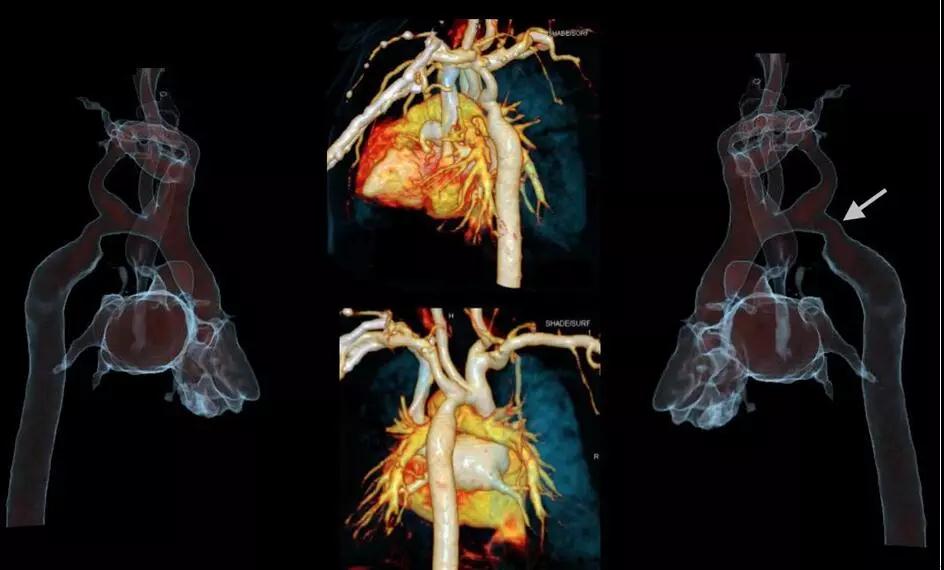

Force CT轉(zhuǎn)速可達(dá)0.25s/圈,雙套球管及探測器交叉90度設(shè)計,相當(dāng)于單源CT 0.125秒每圈,心臟成像時間分辨率66ms,真正跨越自由心跳門檻100ms,因此可以做到自由心率的心臟冠脈CTA等檢查。

西門子獨創(chuàng)的Turbo Flash模式,掃描速度達(dá)每秒73.7cm/s,可在1秒內(nèi)完成胸腹大血管、頭頸心一站式篩查,對胸痛三聯(lián)征、心腦聯(lián)合成像、頭胸心腹部及全程主動脈等多部位一站式聯(lián)合掃描等檢查都能很好的完成。

△66ms單扇區(qū)時間分辨率,任意心率、節(jié)律高清成像

5.1秒一站式多血管同時掃描:

SOMATOMForce 開源CT的73.7厘米/秒的業(yè)內(nèi)最快掃描速度,已突破血流方向相反的成像難題,使得CTA聯(lián)合掃描在血管成像領(lǐng)域應(yīng)用研究將更加深入,未來低輻射和低對比劑量一站式多部位多血管CTA(頭頸冠脈成像、胸痛三聯(lián)征、心臟+腹部血管+下肢血管成像)將成為指導(dǎo)心臟和外周血管性疾病介入診療的重要工具。